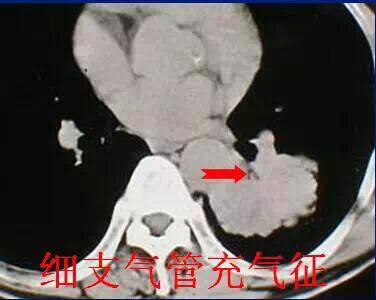

六、细支气管充气征

细条状,直径约1mm的空气密度影,发生率约为33.3%左右。病理基础:扩张的细支气管。